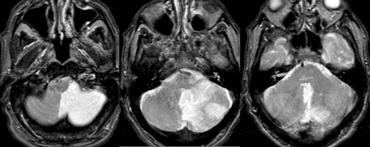

SCA

Bên trái là hình ảnh MRI của nhồi máu tiểu não trong vùng tưới máu của động mạch tiểu não trên, đồng thời có nhồi máu thân não trong vùng tưới máu của PCA.

Lưu ý ranh giới giới hạn tại đường giữa.